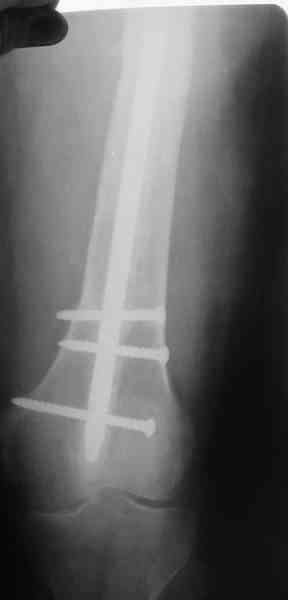

1, 2, 3, 4 - рентгенограммы бедра от 8 августа этого года (через четыре месяца после операции);

В качестве демонстрации лечения канального остеомиелита бедренной кости представляем пациентку (см. parts 2 и 3), которая как раз сегодня была у нас на контрольном осмотре. В мае этого года мы произвели ей фиксацию бедренной кости штифтом-спейсером по поводу ложного сустава и канального остеомиелита бедренной кости. Через 4 недели после операции свищи закрылись. Сейчас она ходит с полной нагрузкой на конечность.

4, 5, 6 - рентгенограммы бедра и фотографии пациентки (прошу прощения за низкое качество рентгеновских снимков) от 7 сентября 2007 г.

Мы уже накопили скромный опыт использования данного способа лечения. С апреля этого года мы выполнили 21 подобную операцию. Мы попробовали применять этот способ при фиксации переломов на фоне различных различных форм остеомиелита, при нагноении мягких тканей и в качестве первичной фиксации при тяжелых открытых переломах при переломах голени, бедра и плеча. В подавляющем большинстве случаев получены хорошие результаты.